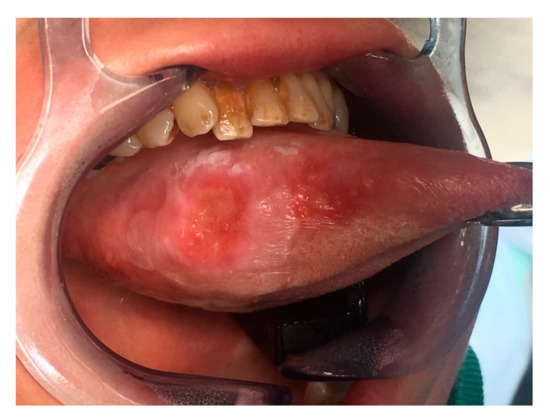

Digital 3D model of Case 2 using Meshlab.

Figure 6.